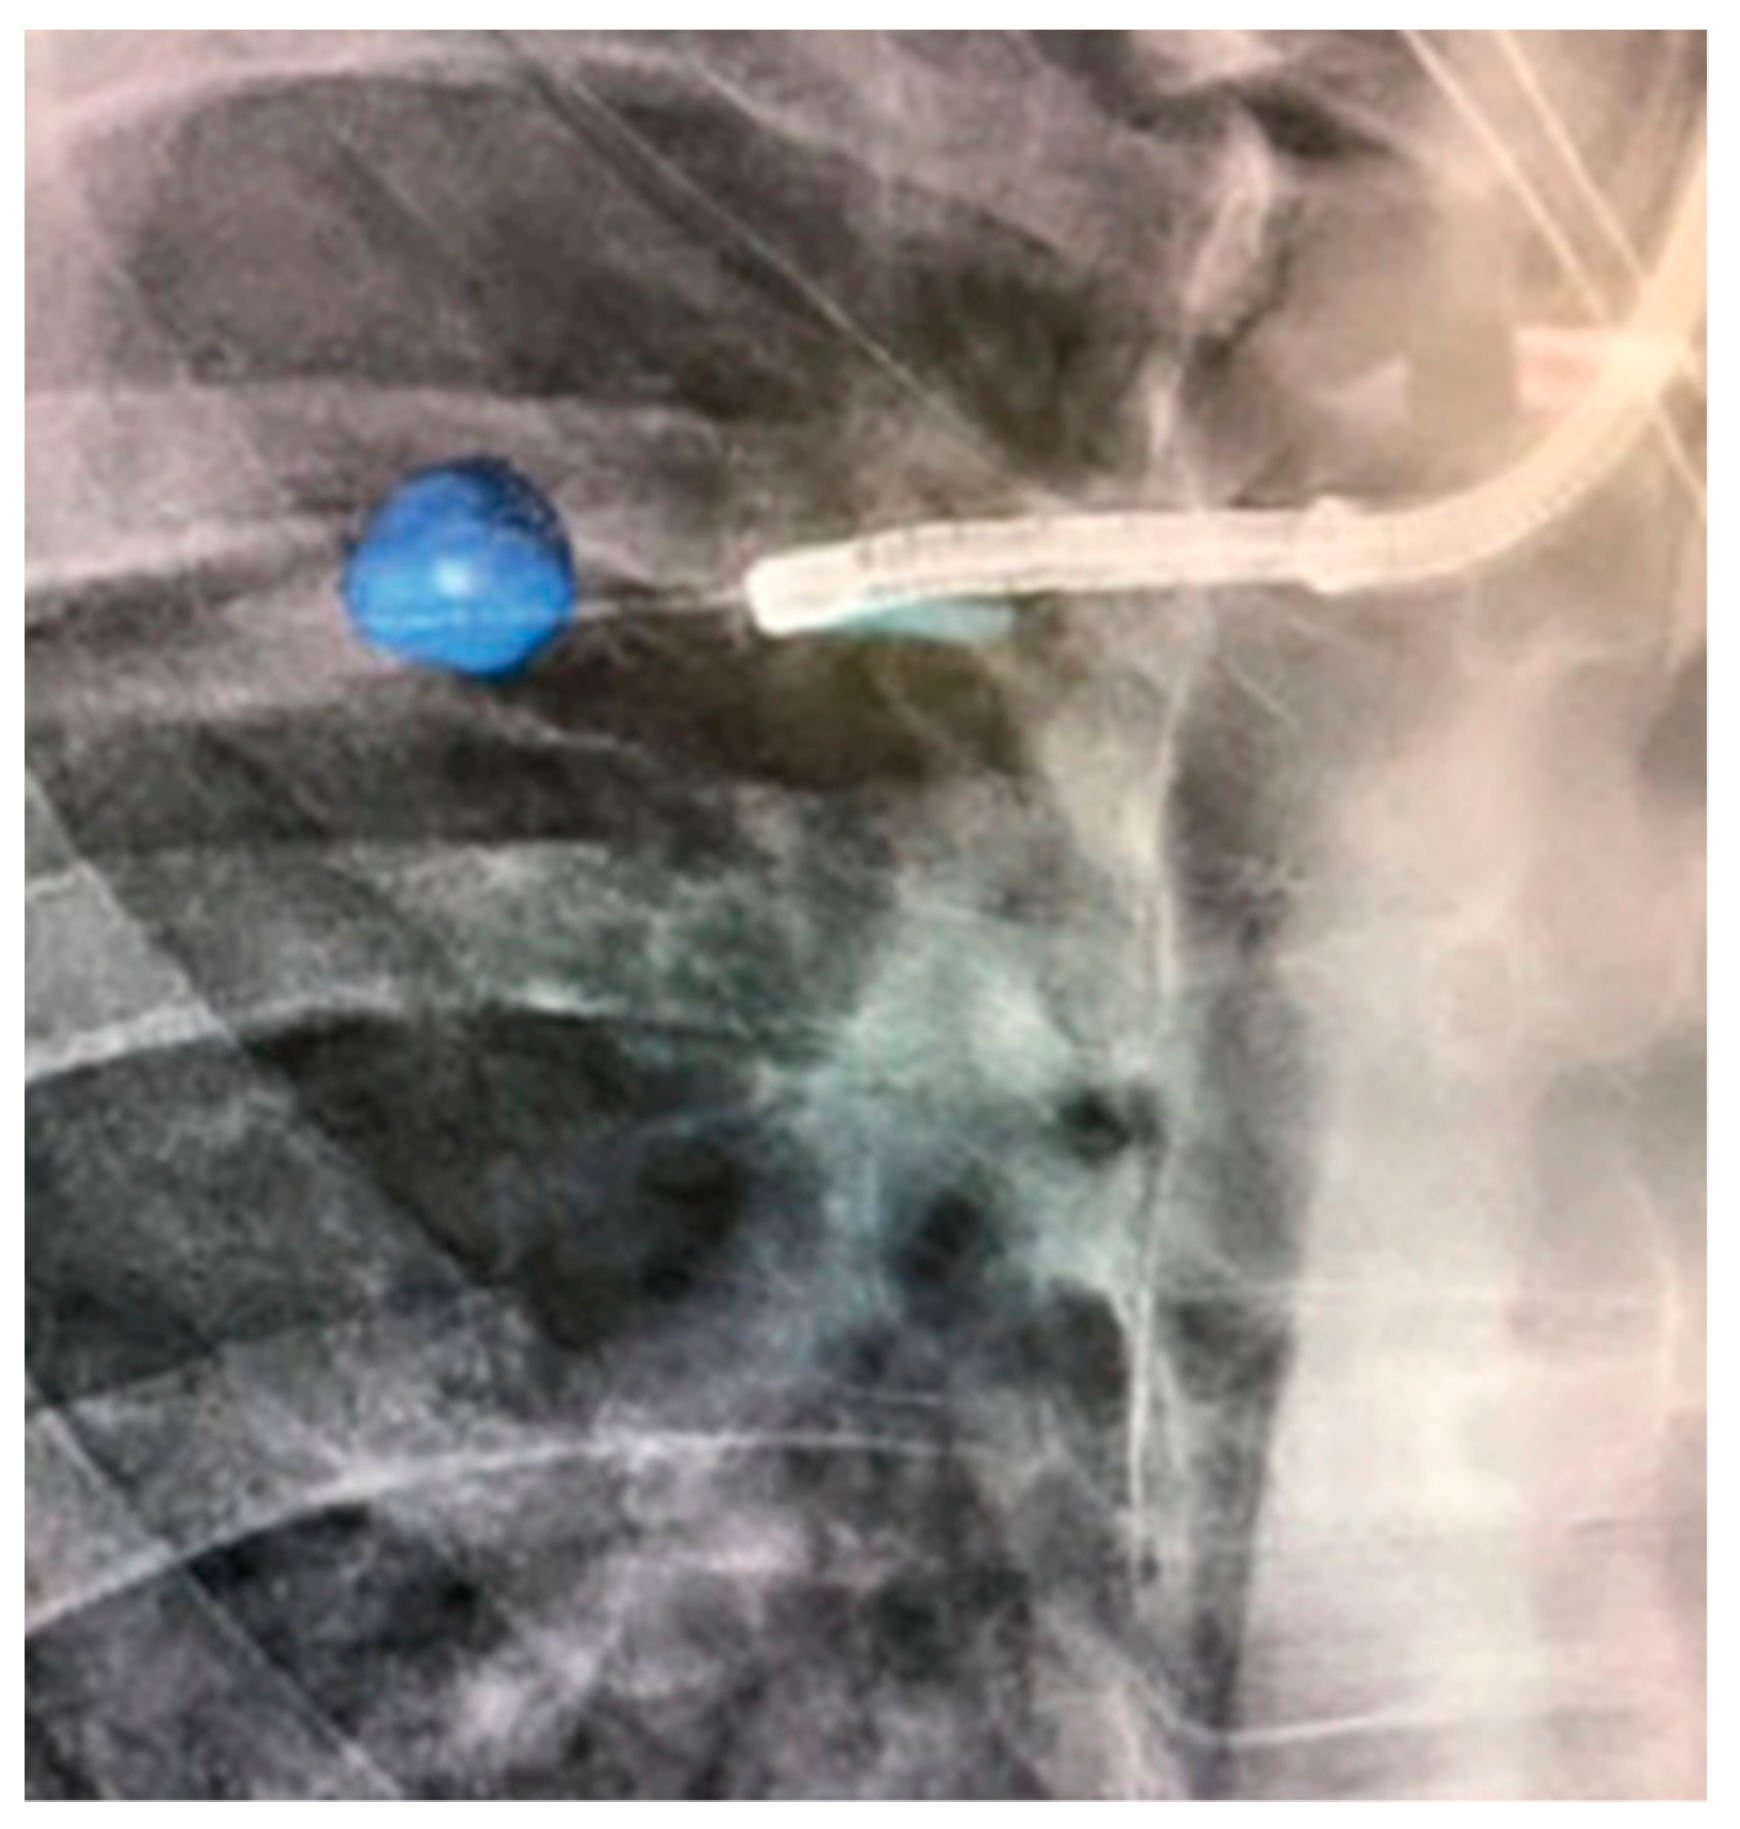

- Chan, J.W.Y.; Chang, A.T.C.; Yu, P.S.Y.; Lau, R.W.H.; Ng, C.S.H. Robotic Assisted-Bronchoscopy with Cone-Beam. CT ICG Dye Marking for Lung Nodule Localization: Experience Beyond USA. Front. Surg. 2022, 9, 943531. [Google Scholar] [CrossRef] [PubMed]

- Chan, J.W.Y.; Lau, R.W.H.; Ngai, J.C.L.; Tsoi, C.; Chu, C.M.; Mok, T.S.K.; Ng, C.S. Transbronchial microwave ablation of lung nodules with electromagnetic navigation bronchoscopy guidance—A novel technique and initial experience with 30 cases. Transl. Lung Cancer Res. 2021, 10, 1608–1622. [Google Scholar] [CrossRef] [PubMed]

- Lau, K.; Spiers, A.; Pritchett, M.; Krimsky, W. P1.05-06 Bronchoscopic Image-Guided Microwave Ablation of Peripheral Lung Tumours—Early Results. J. Thorac. Oncol. 2018, 13, S542. [Google Scholar] [CrossRef]

- Pritchett, M.; Reisenauer, J.; Kern, R.; Wilson, D.S.; Meyers, E.E.; Szapary, P.O.; Laeseke, P.F. Image-Guided Transbronchial Microwave Ablation of Peripheral Primary Lung Tumors with A Flexible Probe: First In Us Experience. Chest 2020, 158, A1452–A1453. [Google Scholar] [CrossRef]